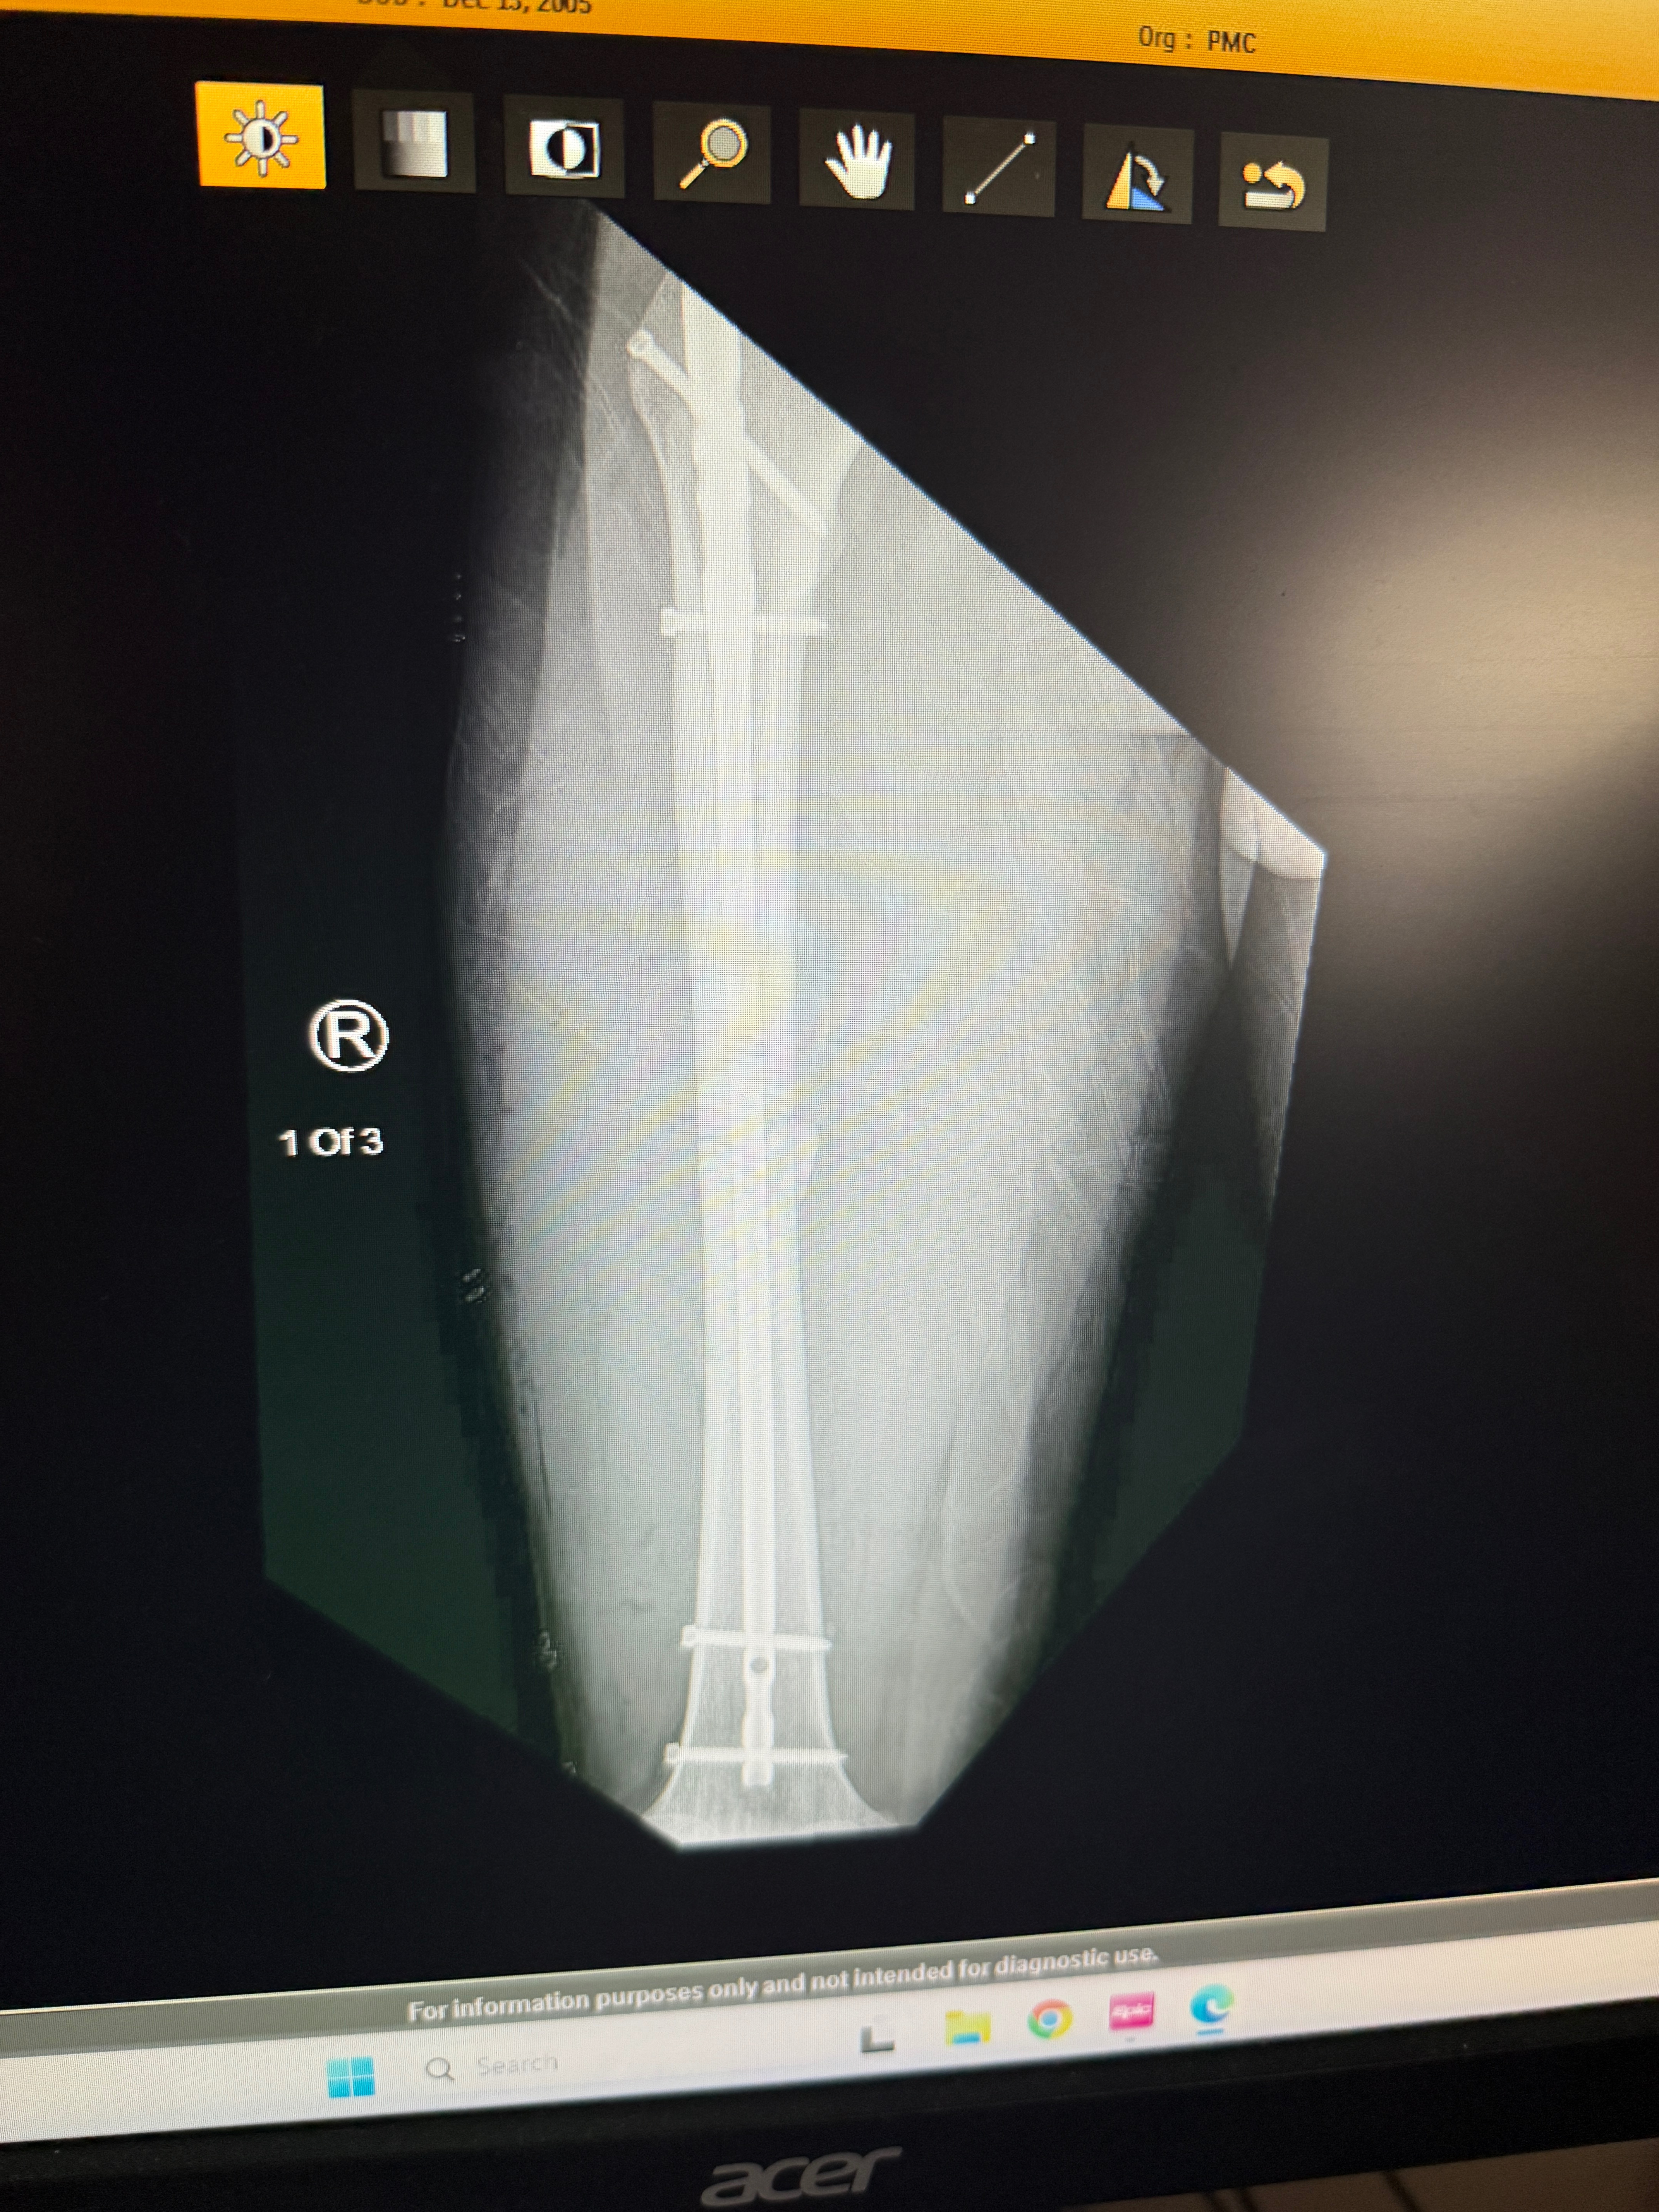

He suffered a severely broken femur—his thigh bone was split in half—and underwent emergency surgery to insert rods and pins into his leg. He is currently still in the hospital, and his next step is intensive, inpatient physical therapy to help him walk again.